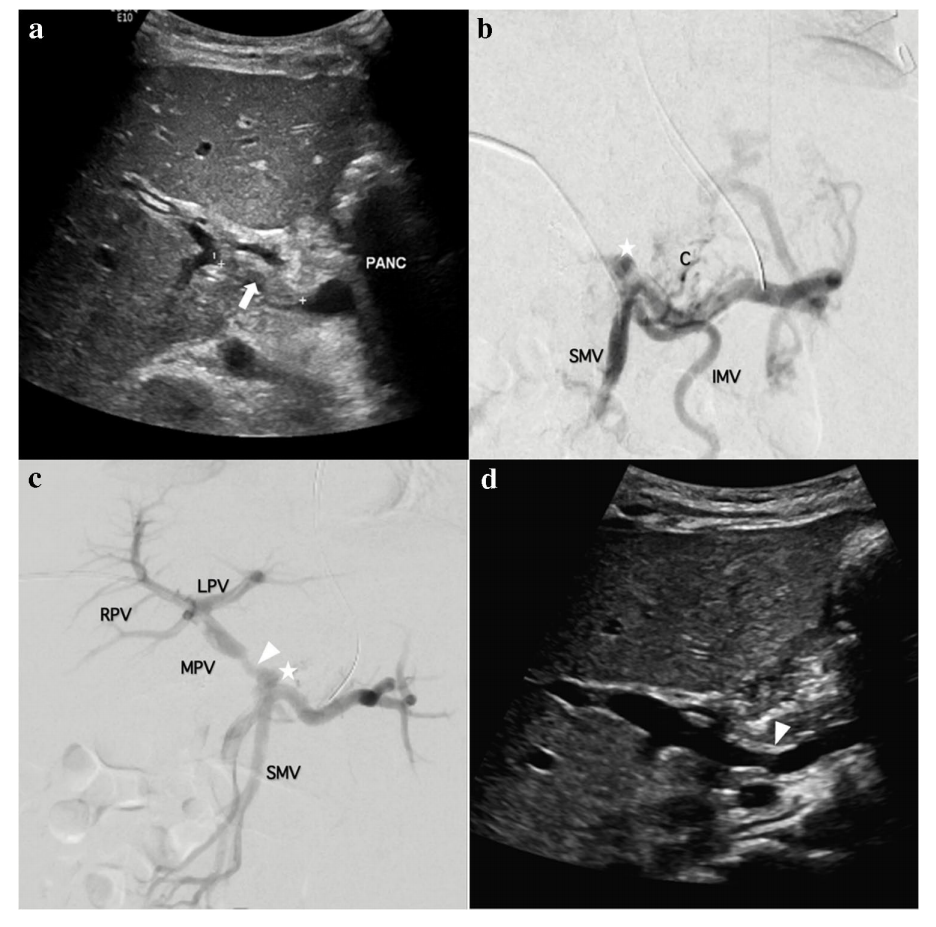

一名九个月大的患儿(8.4 kg)胆道闭锁接受原位肝移植后出现PVT。

图a:介入前,超声显示门静脉内有急性血栓形成(白色箭头)。胰腺头部标记为“PANC”。

图b:介入前,静脉造影显示门静脉闭塞(白星)。

图c:介入后,静脉造影显示门静脉肝内分支血流重新恢复,表明溶栓治疗成功。

图d:介入后,超声显示门静脉再通和血栓切除术后残余狭窄部位(箭头)。